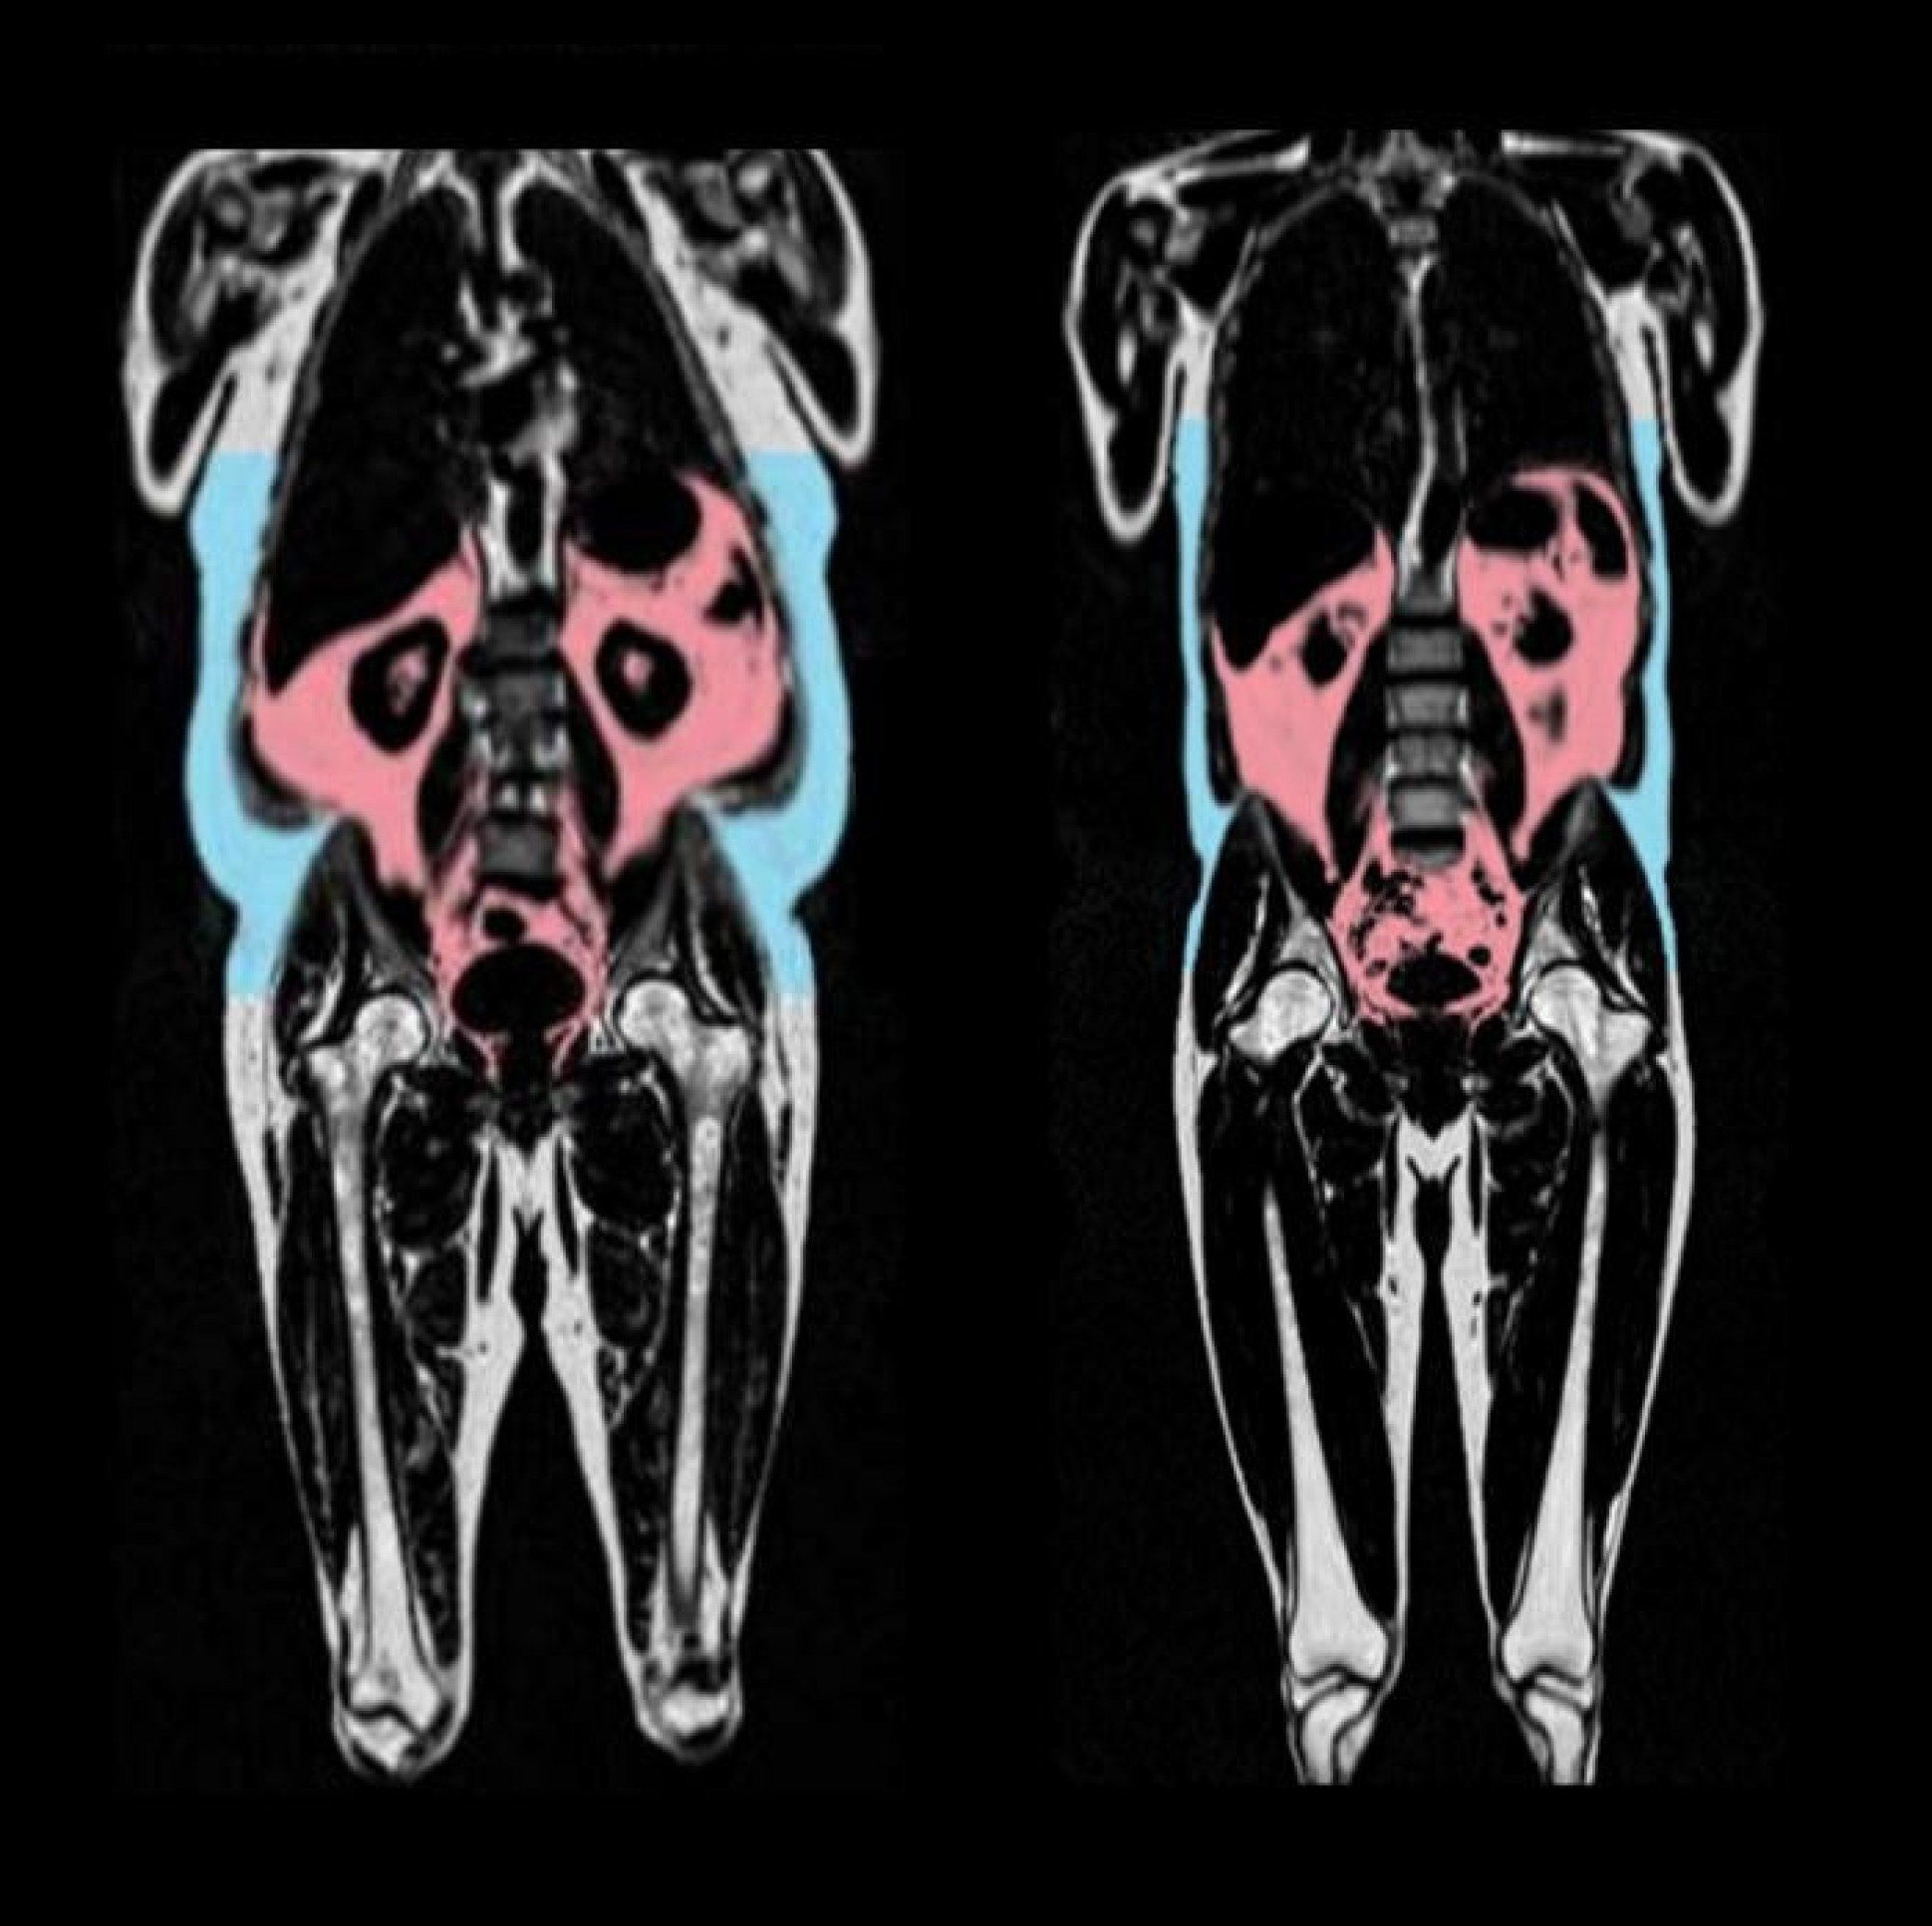

Pesquisadores utilizaram técnicas de ressonância magnética de corpo inteiro e modelos de aprendizado de máquina para prever a chamada "idade cardiovascular", uma medida que compara a idade cronológica da pessoa com sinais de envelhecimento do coração e dos vasos sanguíneos. A diferença entre esses valores foi chamada de “age-delta” no estudo: quanto maior, mais envelhecido está o sistema cardiovascular em relação à idade real.

Os resultados indicam que o acúmulo de gordura visceral (aquela localizada entre os órgãos), a infiltração de gordura nos músculos e o excesso de gordura no fígado estão entre os principais fatores que aceleram o envelhecimento cardiovascular tanto em homens quanto em mulheres.

Nos homens, também foi identificado um efeito negativo da gordura abdominal subcutânea e da chamada gordura androide, que se concentra na região do tronco.

Por outro lado, a gordura ginoide — localizada em quadris e coxas — mostrou-se associada a efeitos protetores, especialmente em mulheres antes da menopausa. Nessas mulheres, a presença desse tipo de gordura esteve ligada a um coração biologicamente mais jovem. Além disso, a massa de gordura total do tronco e do corpo inteiro também apresentou relação positiva em mulheres de todas as idades.

A distribuição da gordura corporal desempenha um papel crucial no envelhecimento cardiovascular, com padrões específicos de gordura associados a mudanças protetoras ou prejudiciais. A gordura visceral (gordura abdominal profunda em torno dos órgãos), a infiltração de gordura no tecido muscular e a fração de gordura hepática são os preditores mais fortes de um aumento na idade cardiovascular (a diferença entre a idade cardiovascular prevista e a idade cronológica) para ambos os sexos. Isso significa que ter mais desses tipos de gordura está associado a um envelhecimento mais rápido do sistema cardiovascular. Em contraste, a gordura ginoide (gordura na parte inferior do corpo, como quadris e coxas) foi associada a uma diminuição da idade cardiovascular em mulheres, sugerindo um papel protetor.

Sim, existem diferenças sexuais notáveis. Embora a gordura visceral, a infiltração de gordura no músculo e a gordura hepática sejam prejudiciais para ambos os sexos, certos depósitos de gordura têm efeitos específicos de sexo. Por exemplo, o volume de tecido adiposo subcutâneo abdominal e a massa gorda androide (gordura na área do tronco) foram associados a um aumento da idade apenas em homens. A gordura ginoide, no entanto, foi associada a uma diminuição da idade cardiovascular em mulheres pré-menopáusicas, mas não pós-menopáusicas, e não teve uma associação significativa em homens. Essa diferença pode ser parcialmente mediada por hormônios sexuais como o estradiol, que pode influenciar a distribuição da gordura e ter efeitos cardioprotetores em mulheres até a menopausa.